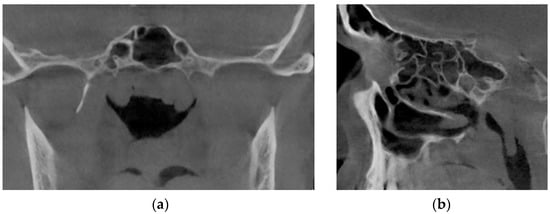

Figure 17 represents tomographic data of a patient with empty nose syndrome after bilateral conchotomy. The removal of the lower shells and enlarged air space in the nasal cavity are clearly visualized in the axial (Figure 17a) and frontal (Figure 17b) projections.

From Figure 18, it can be seen that at the conditional norm (curve 1), the coefficient of aerodynamic nasal resistance along the length of the nasal cavity increases sharply in the initial area (in the area of the nasal valve), and then there is a relatively smooth growth. When the nasal septum is curved (curves 2 and 3), there is a sharp increase in the coefficient of aerodynamic nasal drag in areas with cross-section numbers 17–25 (total length about 16 mm) and 25–28 (total length about 6 mm), respectively. The contribution of local aerodynamic drag, which is associated with the curvature of the nasal septum depending on the size of the area, is significantly larger in Figure 12 than with a more local offset. In chronic rhinosinusitis (curve 4) with generalized thickening of the mucous membrane of the nasal cavity, the coefficient of aerodynamic nasal resistance is greater than in other cases. During adenoid vegetations (curve 5) in the area (27–31, length about 8 mm), there is a rather sharp (but much smaller than in graphs 2 and 3) increase in the coefficient of aerodynamic nasal resistance, due to the location of aerodynamic resistance in a relatively wide distal part nasal cavity at the exit to the nasopharynx (see Figure 16). After conchotomy (curve 6), the aerodynamic resistance of the nasal cavity is significantly reduced and monotonically increases without abrupt changes and extremes, which is caused by a wide air channel.

The data of the functional study using posterior active rhinomanometry (see Figure 19) in the forced respiration actually fully correspond to the obtained analytical calculations in Figure 18. It can be concluded that the lowest air flow is at the curvature of the nasal septum (curves 2 and 3 on Figure 19), especially when the curvature of the nasal septum is in the middle section (curve 2 in Figure 13), which causes significant overlap of air flow by local resistance and subsequent turbulence of the flow for a considerable length. With generalized narrowing of the nasal canal due to chronic rhinosinusitis (curve 4 and Figure 14) there is also a fairly low air flow, but this is achieved due to a greater pressure drop, and as a consequence, the largest of these pathological coefficients of aerodynamic nasal drag with high pressure has a loss in length. Adenoid vegetations (curve 5 and Figure 16), also due to local narrowing in the nasopharynx, contribute to increased aerodynamic nasal resistance, but its increase is significantly (approximately twice) less than in the effects of chronic rhinosinusitis and curvature of the nasal septum.